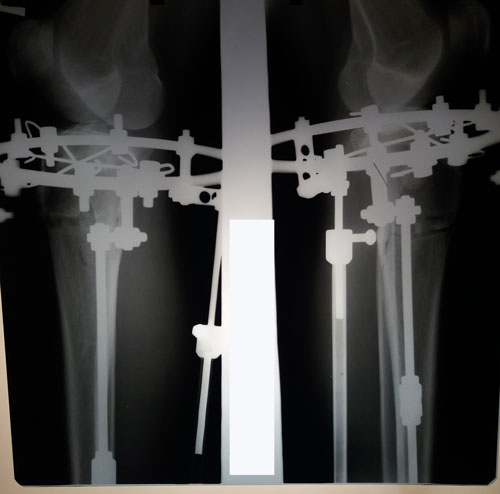

Рентген и ножки в 60 дней.

IMG-20171128-WA0018.jpg

IMG-20171128-WA0021.jpg

IMG-20171128-WA0020.jpg